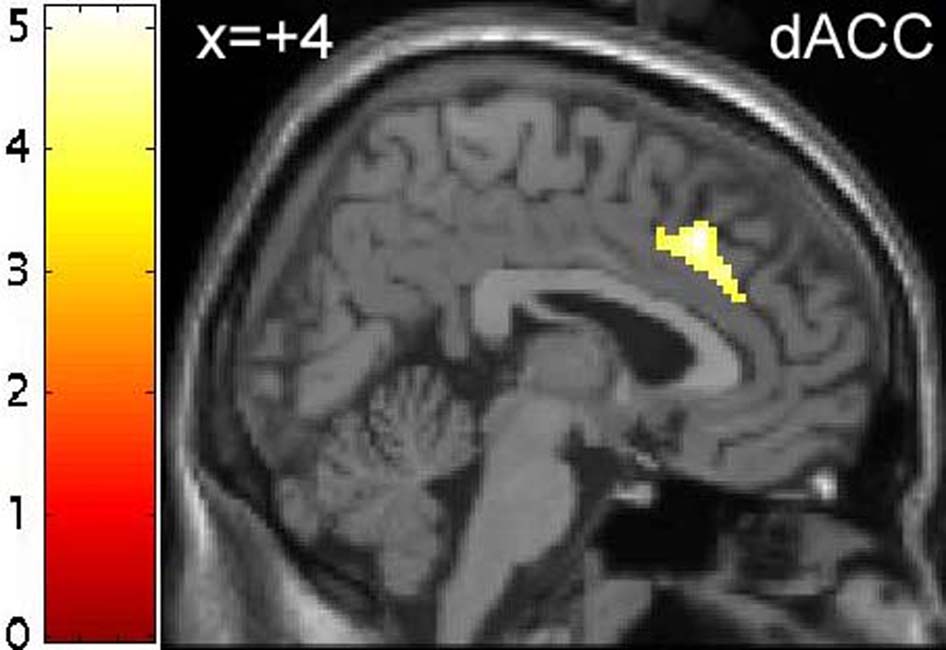

Figure 2. Effect of tryptophan depletion on neural responses to emotional relative to neutral distractor words.

(A) Greater response to emotional relative to neutral distractor words following tryptophan depletion in the left hippocampus ([x=−26, y=−31, z=0], peak Z score=4.07). (C) Greater response to neutral relative to emotional target words following tryptophan depletion in dorsal anterior cingulate cortex ([x=2, y=25, z=36], peak Z score=3.73). Effects in (A) and (C) were significant at p<0.001, minimum cluster size 20 voxels. Color bars indicate t-values and images are thresholded at p<0.001. (B and D) Plots of parameter estimates relative to rest for emotional and neutral distractor words under tryptophan and sham depletion conditions for peak voxels in the left hippocampus (B) and dorsal anterior cingulate (D). Error bars represent 1 SED between emotional and neutral distractors.

BOLD response to emotional relative to neutral distractors was also modulated by ATD in the right dACC, though the interaction was in the opposite direction. The peak voxel of this interaction was contained within an area that showed a greater response to neutral relative to emotional distractors (see above and Table 4 & Table 6). Post-hoc analysis of the parameter estimates for the interaction qualified the main effect, revealing that the greater BOLD response to neutral relative to emotional distractors was only present following TRP−, with no differential response to emotional relative to neutral distractors following TRP+ (see Figures 2c & 2d).